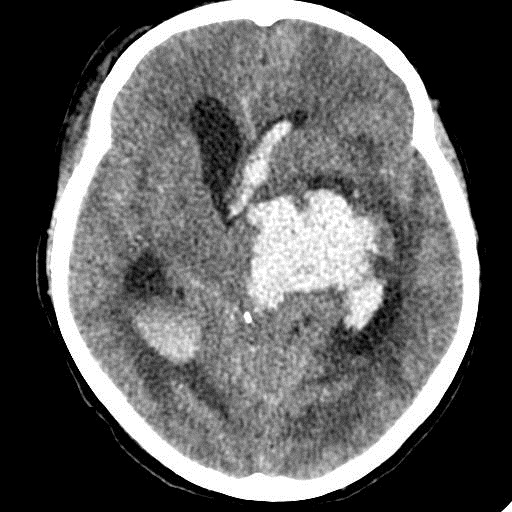

КТ головного мозга, кровоизлияние.

"Скорая" привезла женщину 75 лет, найденную на улице. На КТ направлена с д-зом: кома неясного происхождения. Вот такая картина на КТ.

Острое внутримозговое кровоизлияние с выходом крови в желудочки (боковые - сгустки преимущественно в левом + эффект седиментации с горизонтальным уровнем жидкость\жидкость в задних рогах; сгустки крови в третьем желудочке, кровь в четвертом). Значительное увеличение височных рогов боковых желудочков - гидроцефалия. Смешение срединных структур вправо, отек белого вещества перивентрикулярно слева.

Довольно большие кровоизлияния в стволе мозга (что объясняет тяжесть состояния).

Дифференциация серого и белого в-ва сохраняется, хотя субарахноидальное пространство не прослеживается - проявление масс-эффекта, начальный этап отека мозга.

Остается вопрос по слегка гиперденсному (относительно серго вещества) однородному фокусу в левой лобной доле... и по причине кровоизлияния. Что касается последнего могу предположить патологию базилярной артерии (разрыв аневризмы?)... правда не вижу что-то крови в цистернах основания черепа.

Я написала отек мозга, острое массивное (около 100 мл только внутримозговое) смешанное кровоизлияние слева + в стволе, с прорывом и гемотампонадой желудочков, выраженной латеральной дислокацией (13 мм), менингиома? лобного полюса слева. Убедительных данных за опухоль, давшую кровоизлияние, не вижу, хотя такая мысль тоже была.  Контрастировать такую пациентку никто не будет, агонизирующая(.

У, сколько всего написано. Пока не пришла Nela, поучаствую и я. 1. Кровоизлияние в ткань мозга, а не в опухоль: а)не видно ткани опухоли; б) неясна первичная локализация опухоли (левые базальные ядра?!); в)нет перифокального отека вокруг предролагаемой опухоли, г) при опухолях прорывы в желудочки - редкость; 2) к поперечной дислокации добавил бы безесловную аксиальную: даже цистерна моста сужена, не говоря уже про обходную-четверохолмную и другие; 3) менингиома в левой лобной области, на мой взгляд, сомнительна (кстати, покажите ее пожалуйста), ИМХО - "игра" плотностей;  4) ///метастазы в сосудистые сплетения/// - это очень круто, но они не дали бы внутримозгового кровоизлияния, как и ///плексуспапилома///.

PS. Не очень понял про ///отек мозга///, есть снижение плотности (отек и ишемия) белого вещества левого полушария и задних отделов правого.

Массивное медиальное кровоизлияние с прорывом в желудочки. Кровоизлияние в ствол. Признаки вклинения. В лбу может что-то и есть, но это не принципиально. А может быть и отечные извилины. Смущает, что нет масс-эффекта.

Про отек: субарахноидальных щелей совсем нет, по белому веществу и в стволе снижение плотности, извилины утолщены, серое вещество на этом фоне выглядит более светлым, толстым, подушкообразным.

Причина таких кровоизлияний, как правило, гипертензия и атеросклероз.

Кровоизлияние не связанное с объемным образованием, "гипертоническое", основной массой - в области базальных ядер, кровоизлияние в ствол мозга, кома ясного происхождения :) А менингиома менигниомой, не мешает, так сказать.  Отека мозга здесь небольшой, больше выражено набухание.